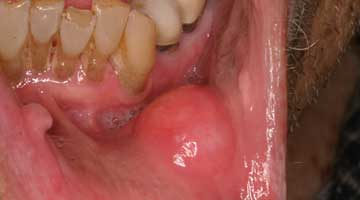

The lips: The lips should be evaluated with the mouth open and closed, noting any abnormalities in symmetry, contour, color, or texture. Attention to the vermilion border of the lower lip is warranted as this is a prime site for oral cancers. First, revert the lower lip and inspect the inner surface. The labial mucosa should be smooth and uniform in color. Notice the frenum of the lip in the midline. Note any signs of smokeless tobacco use (ulcers, red or white discolorations, texture variations) on the labial mucosa. With the lip still retracted, one can also inspect the gingivolabial sulcus, the gingival mucosa, and the teeth. Next, palpate the lip with your thumb and index finger, noting any firm or nodular submucosal areas (figure 1). Repeat these steps for the upper lip.

Figure 1